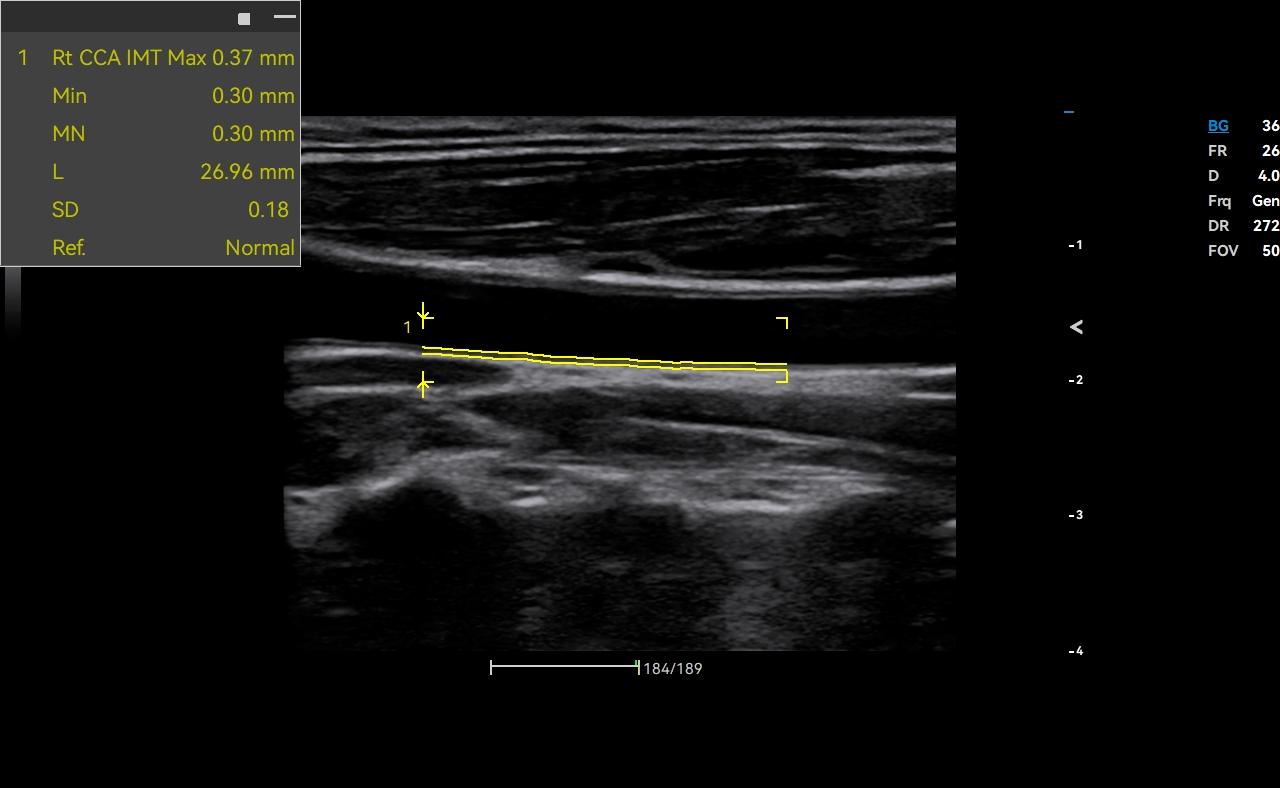

- Category: Color Doppler

Click on images to enlarge

Click on images to enlarge